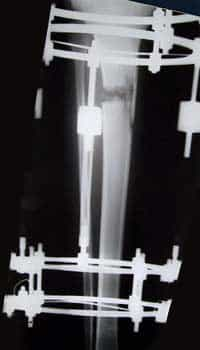

A detta degli esperti questo è un intervento tutt’altro che semplice, con dei rischi come infezioni, trombosi, mancata guarigione dell’osso con necessità di reintervento, lesione dei nervi e dei vasi. Un aggravante poi è dato dalla necessità di operare su entrami gli arti, per non creare differenze significative. Unico caso in cui questo non si presenta è nella cura delle asimmetrie, nelle quali il difetto va corretto su uno solo dei due. Una volta eseguita l’operazione è possibile allungare i segmenti corporei sino a più di un terzo della loro lunghezza iniziale, procedendo alla velocità di circa 1 millimetro al giorno (distrazione lenta e progressiva), dopo aver sezionato l’osso in un punto (osteotomia). Ad esempio, è possibile che un soggetto alto 1.50 metri arrivi fino ad 1.70 metri di altezza: significa un guadagno di ben 20 centimetri. Gli allungamenti si eseguono con varie metodiche. Quelle attualmente più in uso sono quelle che utilizzano fissatori esterni circolari (visibile nella foto sovrastante) per la gamba (tibia-perone) o assiali per il braccio (omero) e per la coscia (femore). A livello femorale è possibile utilizzare in alcuni casi selezionati un chiodo endomidollare (cioè all’interno dell’osso), che permette la graduale distrazione senza necessità di alcun apparato esterno. Il decorso post-operatorio comprende una degenza ospedaliera di circa 5-6 giorni, e controlli clinici e radiografici ad una cadenza di circa 30 giorni. Il paziente può caricare da subito (per quanto tollerato), con i fissatori esterni, mentre deve osservare un carico parziale con 2 stampelle nel caso si sia usato il chiodo endomidollare. La tecnica con questo chiodo, che permette allungamenti del solo femore in un range che varia tra i 6 e i 10 centimetri, ha mostrato brillanti risultati soprattutto in relazione al fatto che tutto il dispositivo è all’interno dell’osso e i disagi legati all’allungamento vengono assai limitati, permettendo così un ritorno rapido alla vita di tutti i giorni. In generale, il tempo di guarigione è di circa 35 giorni per centimetro di allungamento. Nei bambini questo tempo è assai ridotto, talvolta dimezzato in soggetti acondroplasici. L’allungamento attraverso l’uso di fissatori esterni richiede un tempo massimo di rimozione non superiore al periodo di guarigione, mentre questo che si allunga enormemente (fino a 2 anni) con la tecnica del chiodo endomidollare.